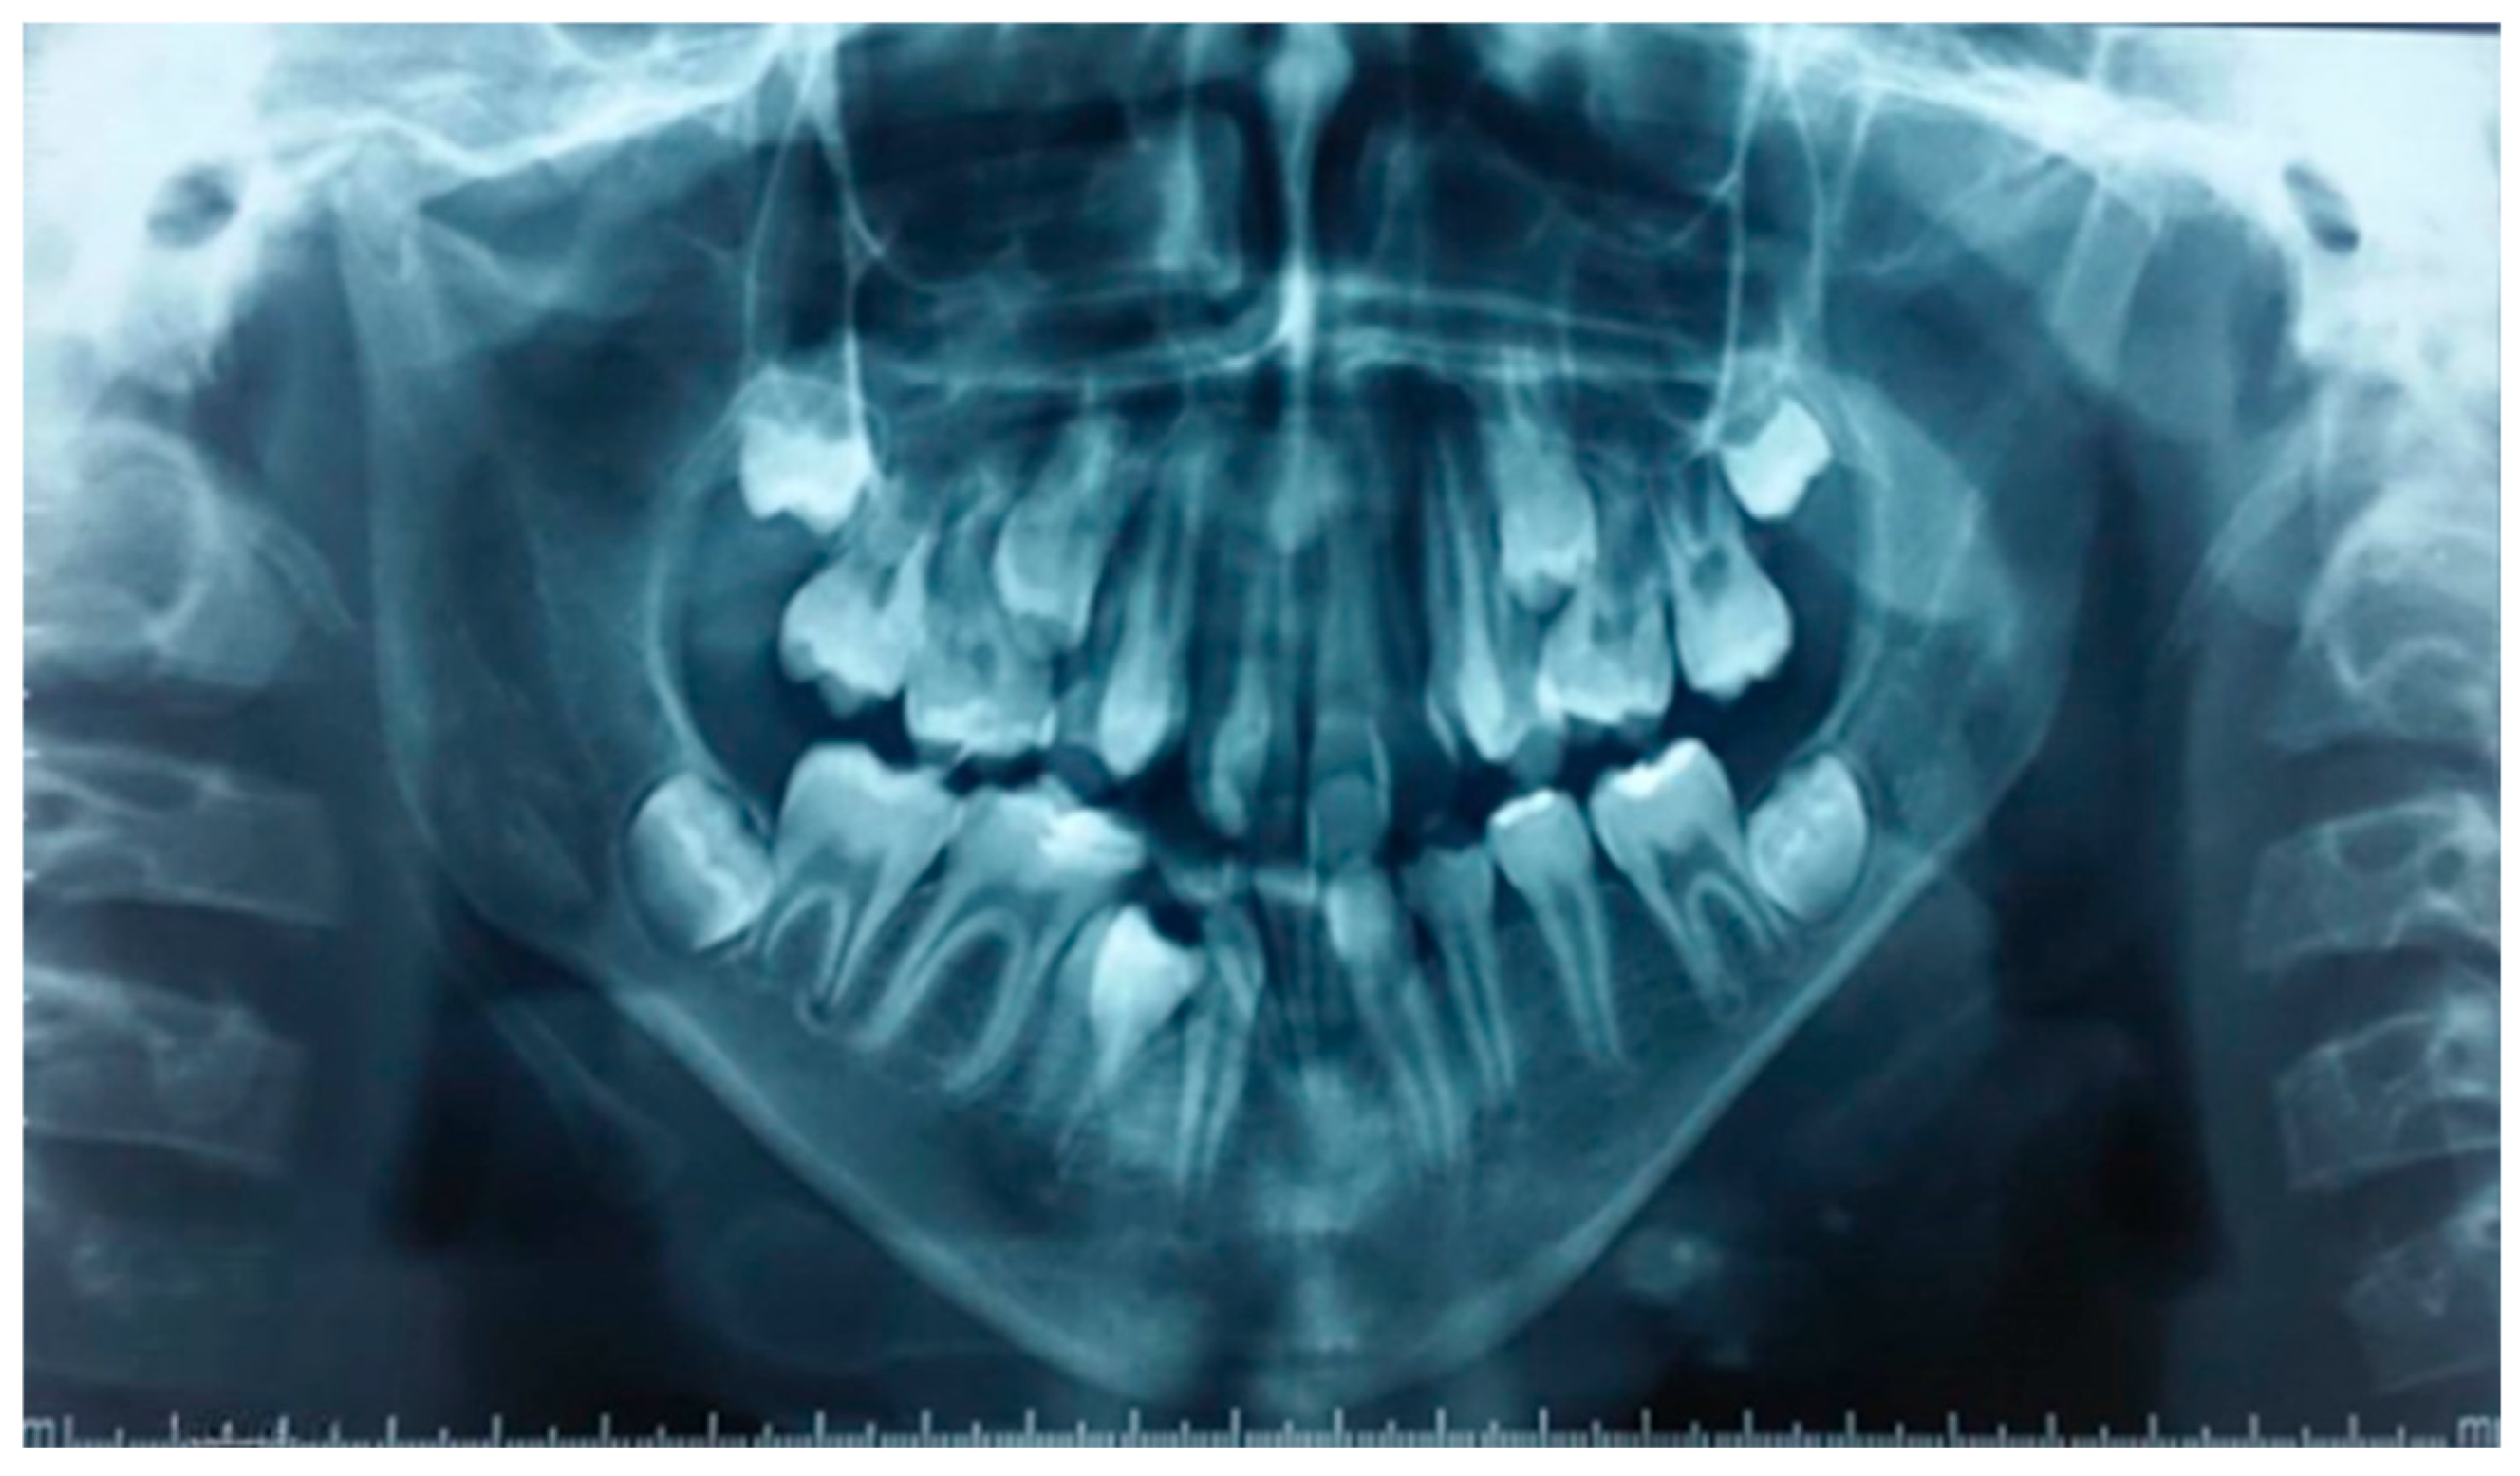

2.4. Intraoral Clinical Examination (Figure 2)

- Maxillary arch: Crowding of the anterior teeth and a distinctive V-shaped arch are associated with the absence of teeth 14 and 24. Notably, the buccal positions of teeth 13 and 23 and the lingual positions of teeth 12 and 22 demonstrate difficulty in finding space and maintaining good symmetry.

- Mandibular arch: Similar crowding and a V-shape in the mandibular arch are accompanied by the absence of teeth 31, 36, and 45, as well as poor positioning of the incisors, reinforcing the skeletal adaptations caused by the lack of lingual function.

- Interarch relationships: Class III canine and molar relationships characterize a reverse overjet between teeth 26 and 36, with both maxillary and mandibular arches showing endognathia, a hallmark of altered growth patterns.